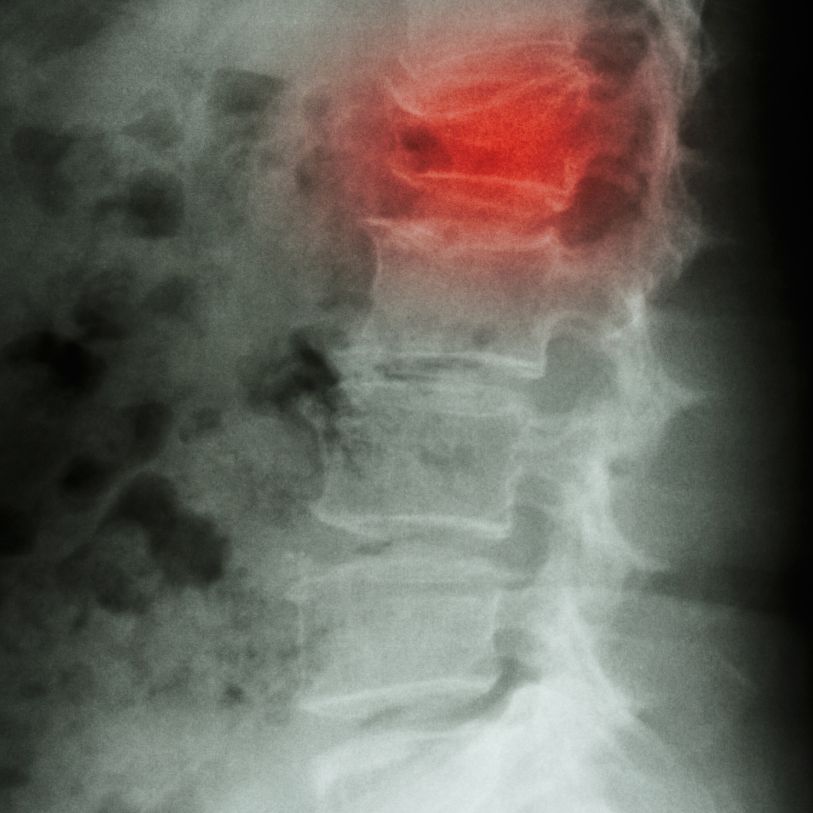

Presión vertebral y riesgo de fracturas por compresión

Muchas personas mayores han sufrido, sin saberlo, pequeños aplastamientos o fracturas por compresión vertebral, especialmente en la charnela dorsolumbar. En su momento, estos episodios se vivieron simplemente como un dolor de espalda más, una lumbalgia pasajera que no pareció tener mayor importancia. Sin embargo, con los años, estas alteraciones pueden contribuir a que la columna pierda altura y se encorve progresivamente, afectando a la postura, la respiración y la autonomía. En muchos casos, este hallazgo sólo se descubre de forma casual en una radiografía realizada por otro motivo. Por eso insistimos tanto en la prevención y la anticipación, no solo para las personas mayores, sino también para sus hijos, que hoy pueden actuar a tiempo para proteger su columna y evitar repetir la misma historia.

Estas fracturas:

- no siempre se producen tras un traumatismo importante,

- pueden desarrollarse de forma progresiva,

- a menudo se manifiestan como dolor persistente, rigidez o pérdida de movilidad.

Por ello, el dolor repetido en esta región merece siempre una valoración adecuada, siempre con exámenes complementarios como una radiografía, escáner, o una osteodensitometría.